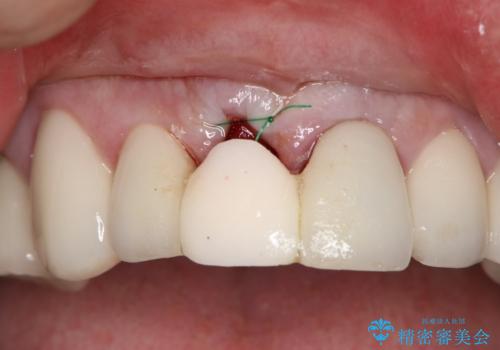

患者様のご要望もあり、審美性の確保ができる抜歯早期埋入→埋入後即時荷重という手術法を取りました。

費用面では通常埋入と比べ若干高価にはなりますが、手術後のストレスがかなり軽減されトータルで患者様にとってメリットの多い治療法であるといえると思います。

それと比較すると、今回の方法では骨にしっかりと固定されているインプラントに単独で仮歯を装着することができるためフロスも通せますし、ある程度負荷のかかる食事も気にせずできるようになります。